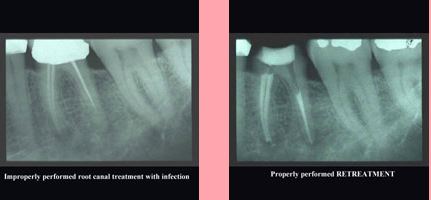

The photograph on the left shows an improperly performed root canal treatment with an infection.

The photograph on the right shows a properly performed RETREATMENT.